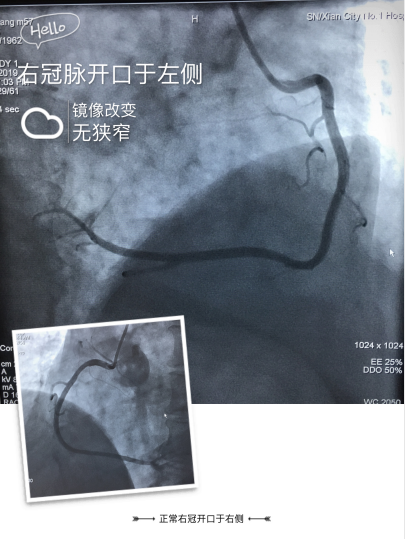

面对首例右位心冠脉造影手术,为保障手术顺利、安全进行,我科赵朝主任召集心血管病成人导航 程曼丽院长等医务团队开展术前讨论,就手术中可能遇到的问题制定解决方案,1如果常规的冠脉造影导管不能顺利完成,那么需要准备特殊类型的造影导管,2若病情需要支架置入治疗,可能需要准备特殊耗材,如Amplatz Right1.0、Amplatz Left1.0、XB Right 1.0、XB Right 1.0、Extra Rackup Right1.0等;充分的准备后,于2019-09-04由心内三赵朝主任,陆艳副主任医师带领团队行右位心冠脉造影术,术中通过JR4.0造影导管在左冠状窦内找到右冠状动脉开口,造影显示血管光滑无狭窄。以JL4.0造影导管在右冠窦内找到左冠状动脉开口,造影显示血管光滑无狭窄。明确排除了患者冠心病诊断,治疗做出相应调整,考虑症状可能与冠脉痉挛等功能性改变引起,积极加强改善痉挛、改善心肌代谢、改善症状治疗。排除冠心病并给予适当的心理疏导后,患者症状逐渐减轻出院。我科在充分的准备工作后,顺利完成了首例右位心的冠脉造影术,积累了宝贵的手术经验,保障了患者生命安全。